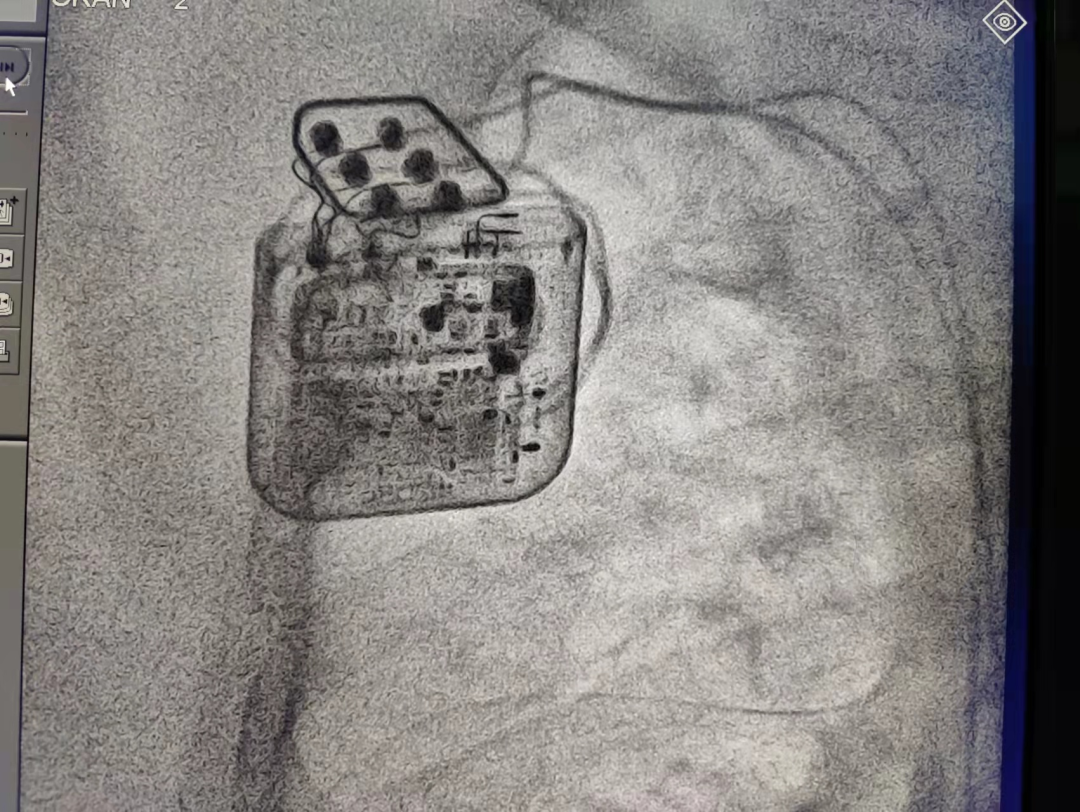

CCM植入手术和传统起搏器植入并无大的差异。首先准备静脉通路,右锁骨下静脉穿刺,送入导丝,并在透视下确认钢丝进入右心系统;之后进行囊袋制作,切开皮肤,分离皮下组织至胸大肌筋膜,并在切口下方制作与脉冲发生器大小相适应的囊袋 ,并彻底止血。植入起搏导线,两根RV导线均植入在右心室间隔,同时,RV导线之间距离2cm以上,分别测试两根RV导线的起搏阈值)和起搏阻抗。导线固定后,令患者咳嗽以保证导管电极在心腔内位置稳定,张力合适。连接导线与脉冲发生器连接,设定输出为7.5V,询问患者是否有不舒感,患者体感良好。之后,将脉冲发生器埋于预先制作的囊袋中,逐层缝合。患者未诉胸痛心悸等不适症状,患者心脏的室壁运动明显增强,手术圆满成功。耗时55分钟。